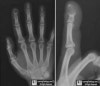

원위 지골(distal phalanx)가 가장 흔한 골성 부위입니다.

낭종은 손톱 기저부에 나타나며 X-ray상 내연골종(enchondroma)처럼 보입니다.

피질골(cortical bone)은 확장되어 있으며, 중심부의 용해성 병변이 유일한 골성 반응입니다.

X-ray : 손의 표피 낭종(Epidermal cyst in the hand)